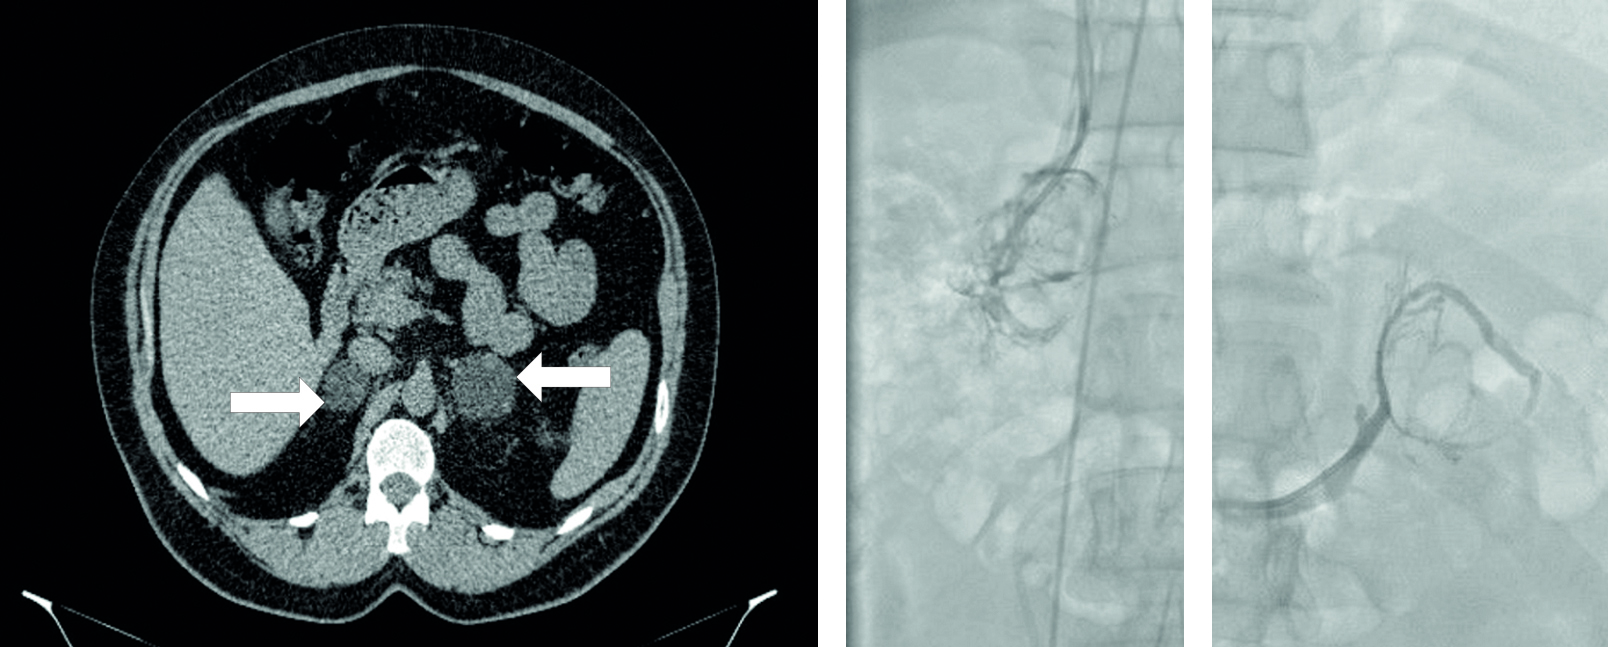

У больных с автономной секрецией кортизола отмечалось соответствие увеличения томографических размеров надпочечника с преобладанием выработки кортизола. В то время как у одной больной с синдромом Кушинга (вторая группа) была диагностирована латерализация на стороне с меньшими размерами железы (рисунок 2).

На рисунке 2.1 представлена томографическая картина правого и левого надпочечника, 2.2 – венография правого надпочечника, 2.3 – венография левого надпочечника

Рисунок 2. КТ органов брюшной полости и забрюшинного пространства (аксиальный срез, нативная фаза) и ангиография правого и левого надпочечников у пациентки с БМНГ с синдромом Кушинга.

Figure 2. Abdominal and retroperitoneal CT scan (axial view, native phase) and angiography of the right and left adrenal glands in a patient with bilateral macronodular adrenal hyperplasia with Cushing's syndrome.

По результатам ССВЗК у этой пациентки была получена правосторонняя латерализация, где Li=7,57 и контрлатеральный индекс составил 3,22. Расчетные градиенты латерализации по кортизолу F, кортикостерону В и 11-дезоксикортизолу S, полученные методом ВЭЖХ, свидетельствовали о доминировании правого надпочечника (Fд/Fк=5,43, Bд/Bк=2,28, Sд/Sк=2,82).